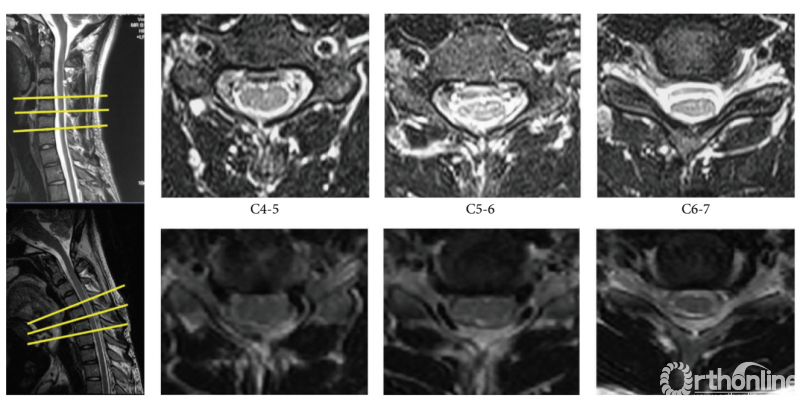

相对于颈椎中立位X/Y值,在G2-G5组的C4-5节段,屈颈后观察到明显X/Y值增加;上述测量值异常增加也出现在所有患者组(G1-G5)的C5-6及C6-7节段(图2,P<0.05)。而在C7-T1节段,屈颈后X/Y值的明显增加,仅发生在病程超过4年的患者中(G5组)。此外,屈颈位X/Y值在5组患者间(G1-G5)也存在显著差异(P=0.022,图3)。

图2:1例18岁男性平山病患者,T2加权矢状位和横断面图像显示屈颈后出现明显“膜壁分离”现象